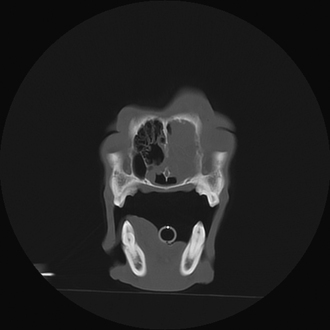

Radiography

Radiographic imaging or CT is always performed before rhinoscopy. Rhinoscopic iatrogenic hemorrhaging and irrigation fluid used during the procedure will distort tissue and create fluid densities that can influence the findings in any radiographic study. Nasal radiographs can be performed in most hospitals and, with practice, can be very useful in the localization and characterization of nasal and nasopharyngeal disease.5 Nasal radiographs require general anesthesia and special patient positioning. Most commonly performed are 30-degree beam-angled open-mouth ventrodorsal and straight lateral views. The open-mouth view provides a complete, symmetrical image of the nasal cavity without superimposition of the mandible. Tumors typically show asymmetrical opacities and turbinate destruction (Figure 19-6). Turbinate destruction is also seen with fungal rhinitis. The straight lateral view allows evaluation of the nasopharynx and frontal sinuses (Figure 19-7). Further study of the frontal sinuses is achieved with a rostrocaudal tangential view (Figure 19-8). This allows comparison of the left and right frontal sinuses as the cavities are superimposed on the lateral view. Dental films of the maxillary arcade are sometimes needed to rule out tooth root abscesses and oronasal fistulae. MRI and CT scans are becoming more commonly available and provide better detail of the nasal, nasopharyngeal, and sinus cavities and cranial vault anatomy compared with standard radiography.6,7 Advanced imaging via MRI and CT, although considered state of the art, assist in description and localization of diseased tissue but have not yet produced results specific enough to eliminate the need for rhinoscopy8,9 (Figures 19-9 through 19-11) (Table 19-1).

image

Figure 19-9 Feline skull computed tomography image with nasopharyngeal mass.